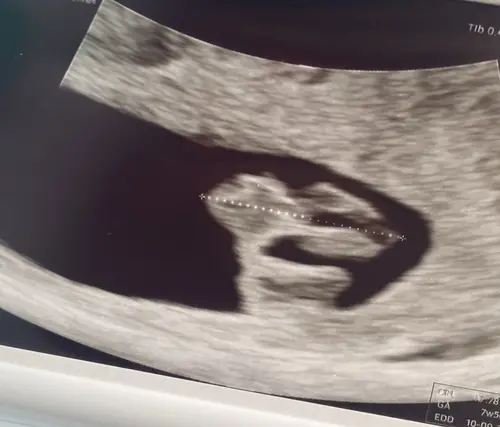

7w5d 馃槃 Dit was onze eerste echo